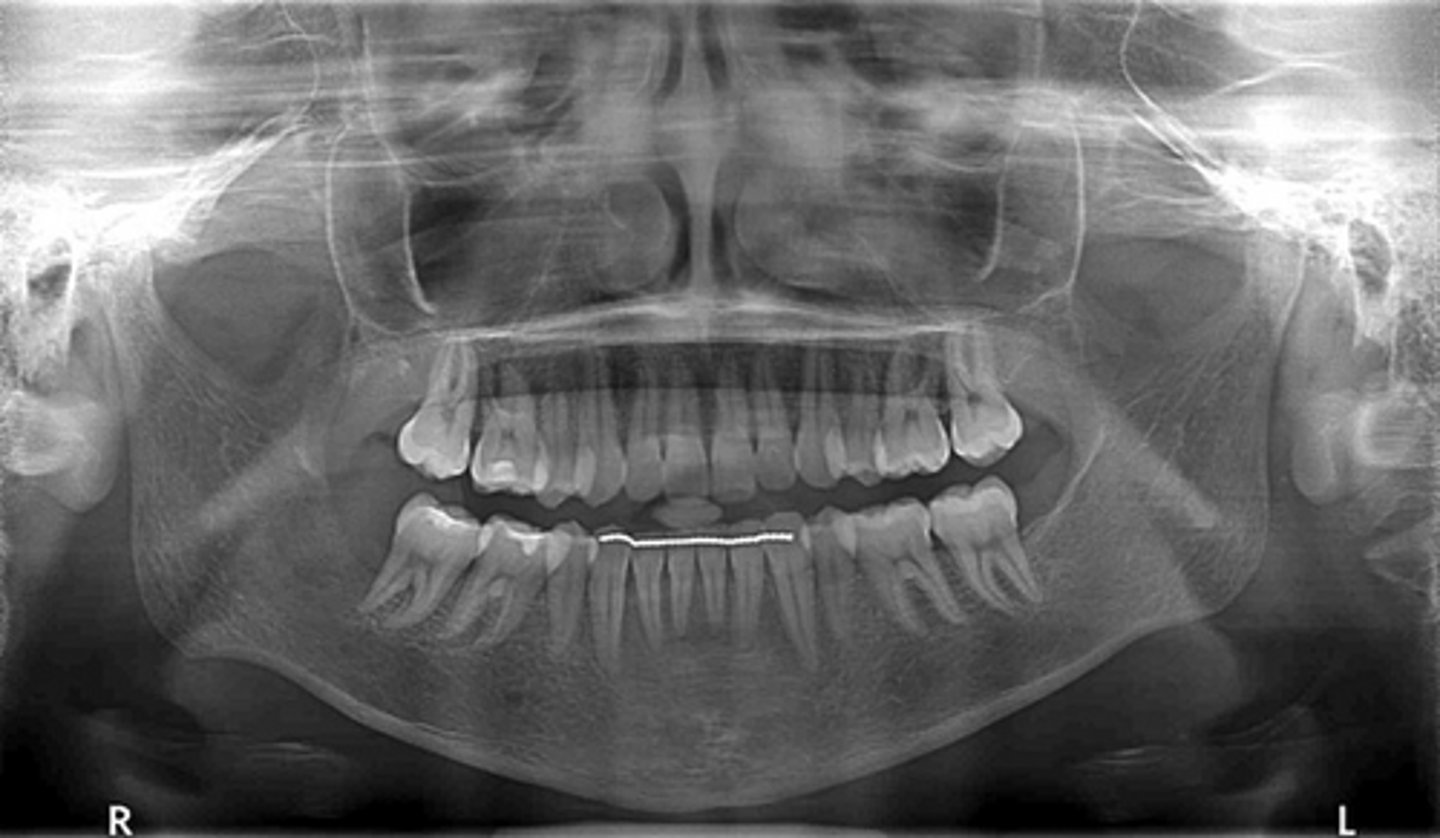

The radiograph depicts a sinus graft with irregular radiodensity, the discontinuity of the bone integration might impact implant treatment.

What does the radiograph show and how might it impact dental treatment?